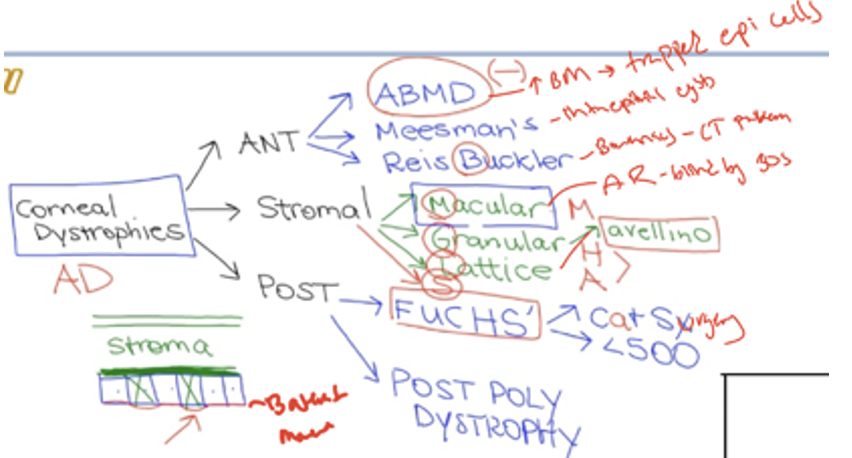

Epithelium Dystrophies

Epithelial Basement Membrane Dystrophy: Abnormal excessive basement membrane

Messman Dystrophy: Bilateral clear intraepithelial cysts spread diffusely across cornea

Reis Buckler’s Dystrophy: abnormal development of Bowman’s with collagen.

Thiel Behnke: honeycomb opacities in Bowmans and stroma

Stromal Dystrophy

Macular Dystrophy (AR) - diffuse central superficial stromal with grey opacities. Stromal haze by 5-9. Blindness by 20s

Granular Dystrophy: small, white, crumb-like deposits to form in the cornea's middle layer.

Lattice Dystrophy: deposition of amyloid resulting in steadily progressive loss of vision

Endothelium/descemet dystrophy

Fuchs endothelial dystrophy: inc in post lamina production causing guttata on BM of endo. This results in dec endo cell (<500 cells/mm2) resulting in stomal edema. Female over 60

Posterior Polymorphous Dystrophy: endo changes shape bc descemet pushes on it.